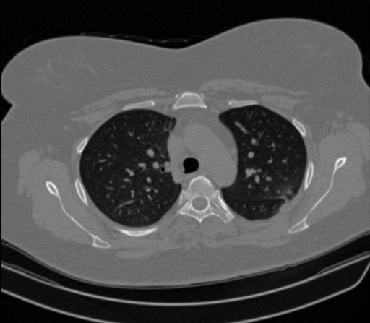

Figure 1 shows four CT scan slices, two from a non-COVID-19 CT scan, on the left and two from a COVID-19 scan, on the right. Bilateral ground glass regions are seen especially in lower lung lobes in the COVID-19 slices.